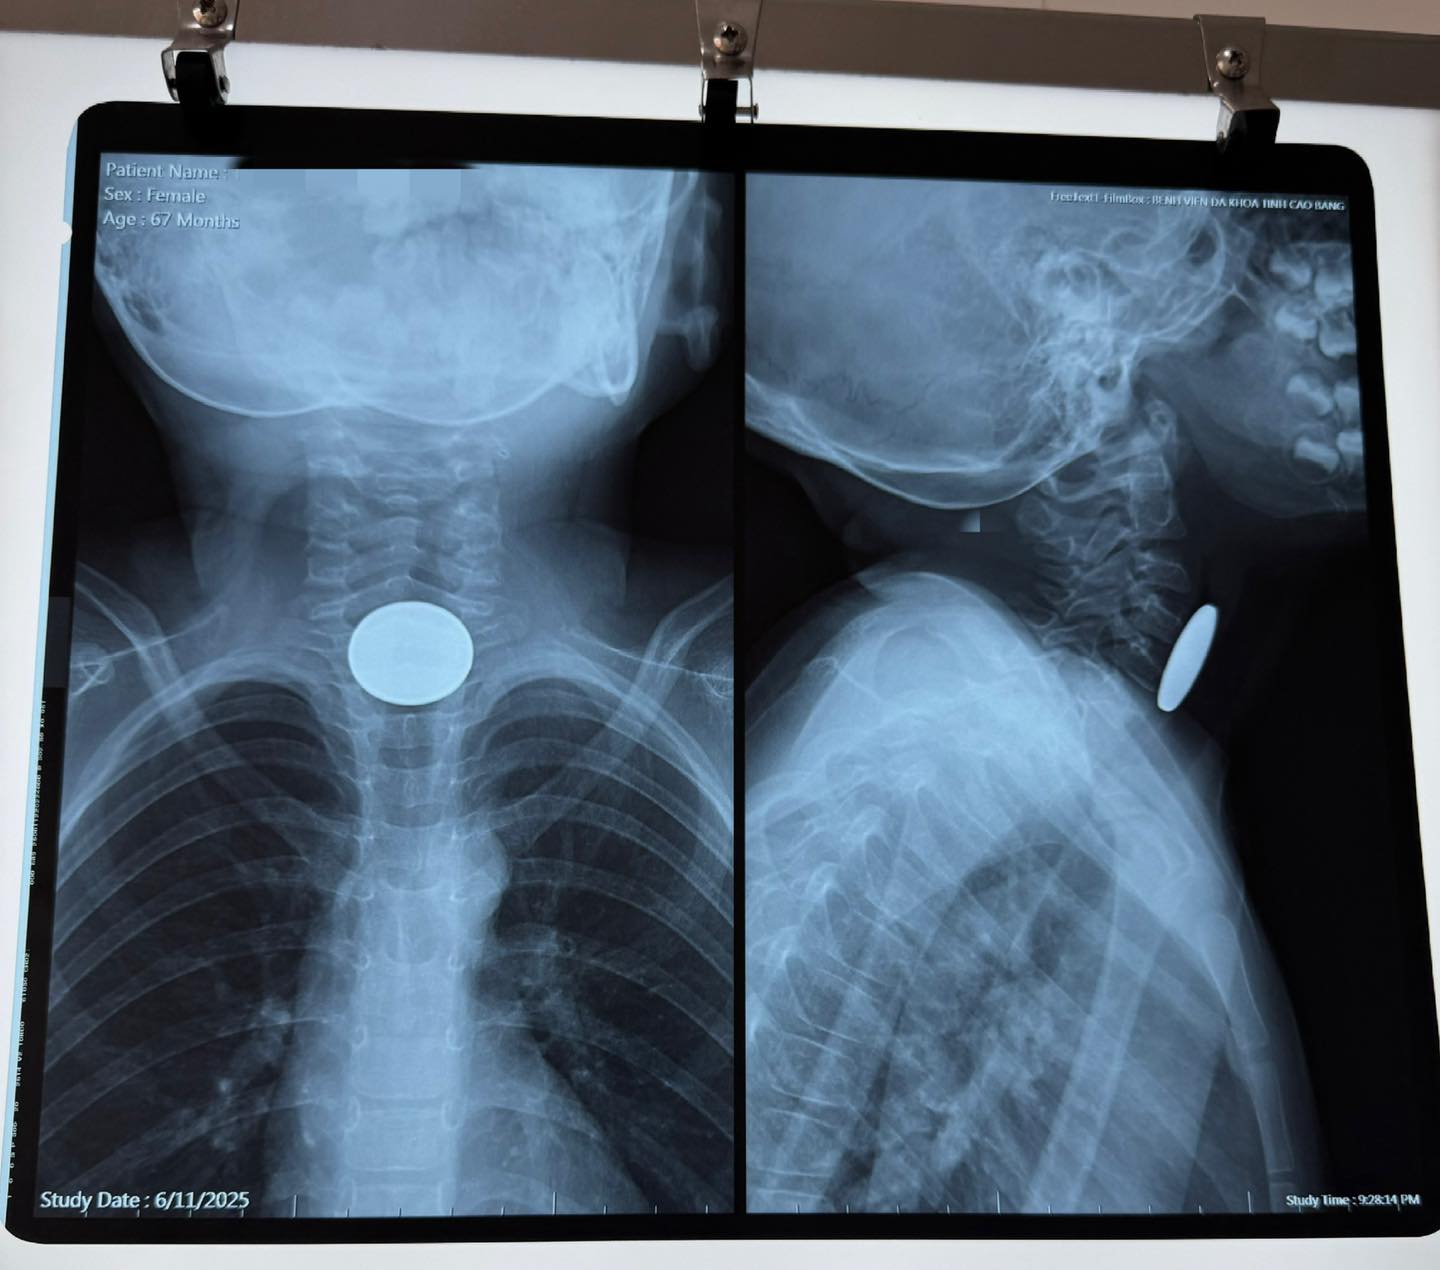

Theo thông tin từ kíp trực, sau khi thăm khám và hội chẩn khẩn cấp, các bác sĩ xác định có dị vật đường tiêu hóa trên, nghi nằm trong thực quản. Ngay trong đêm, ekip gây mê và các bác sĩ Tai Mũi Họng đã tiến hành nội soi thực quản ống cứng cấp cứu. Dị vật được xác định là một đồng xu kim loại màu trắng, đường kính khoảng 2,5 cm, mắc cách cung răng trên khoảng 12 cm. Dị vật được lấy ra an toàn bằng dụng cụ chuyên dụng. Sau nội soi kiểm tra lại, không phát hiện tổn thương thực quản, niêm mạc hồng, không viêm loét hay chảy máu. Thủ thuật kết thúc an toàn, không có biến chứng.

Hình ảnh dị vật đồng xu trên phim chụp.